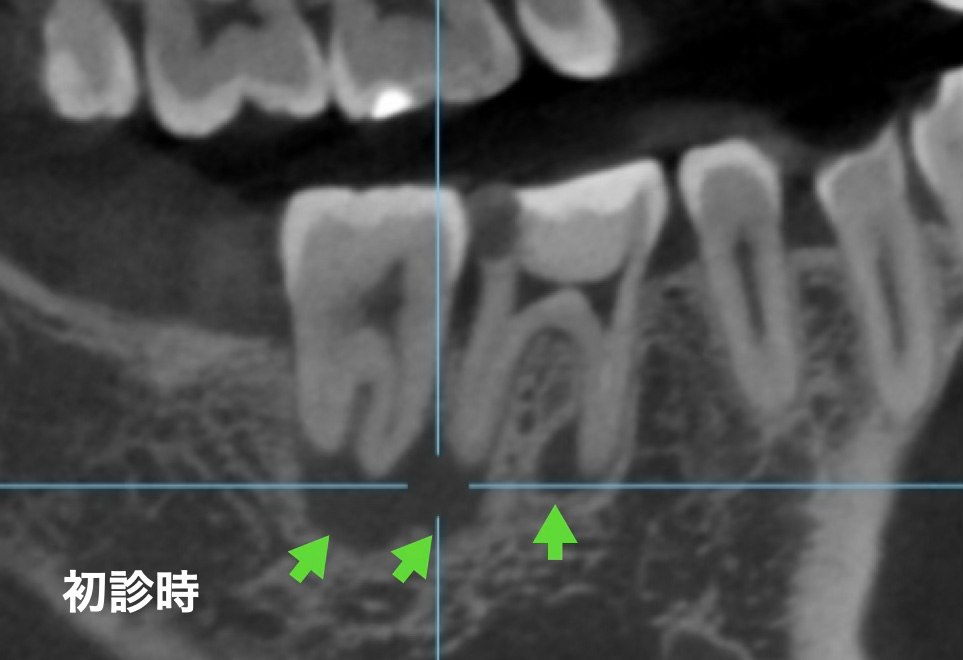

では次にレントゲン写真とCT写真の状態です。

レントゲン写真より、根の先の影(透過像)が後ろの奥の第二大臼歯のところまで広がっているように見えます。またレントゲンからの隣の歯と接する部分の歯が薄くなっています。

実際に透過像の範囲は第二大臼歯まで及んでおり、第二大臼歯の歯髄も死んでしまっている可能性も考えられました。そのため、コールドテストと言って歯に冷たい刺激を加えて歯髄の反応を確認しました。加えて歯髄電気診という微弱は電気刺激を第二大臼歯に加えたところ、歯髄は正常な反応を示したため、CT及び複合的な検査から第一大臼歯由来の透過像として、精密根管治療を開始しました。

初めの治療から早くも2年以上が経過しました。その経過を確認するためにCTを撮影しました。初診時の矢印部分を見ていただければおわかりいただけると思いますが、透過像がなくなり、骨がしっかりと再生して治っているのがわかります。